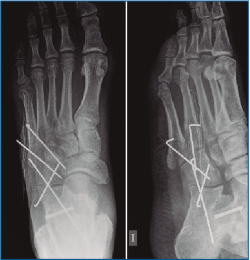

En la exploración destaca una inflamación y dolor en el borde externo del pie que no impide la deambulación. En la revisión de las pruebas complementarias (radiografía simple y TC) se confirman las lesiones previamente diagnosticadas, junto con una luxación del cuboides plantomedial (Figuras 1 y 2).

Figura 1. Radiografía prequirúrgica a la semana de evolución del traumatismo. Obsérvese el desplazamiento medial del cuboides.

Es intervenido a la semana de la lesión realizándose, bajo anestesia raquídea e isquemia del miembro, una incisión dorsolateral desde la articulación calcaneocuboidea hasta la base del 4.º MTT. Se expuso el cuboides reflejando el extensor corto a dorsal y peroneo corto a plantar y se evidenció la desalineación del cuboides con el 4.º y 5.º MTT y el calcáneo creada por la luxación. Se realizó una reducción manual del mismo y una fijación con 2 agujas de Kirschner (agujas K) metatarsocuboideas, 1 aguja cuboideocalcánea y 1 calcaneocuboidea, realizándose al mismo tiempo una fijación de la apófisis lateral del astrágalo con un tornillo canulado (Figuras 3, 4 y 5). Se mantuvo 6 semanas inmovilizado, momento en el que se retiraron las agujas K. A la 6.ª semana, se inicia la carga con ortesis de carga hasta la 8.ª semana.

Figura 5. Imagen intraoperatoria de la reducción del cuboides y fijación con 2 agujas de Kirschner metatarsocuboideas, 1 aguja cuboideocalcanea y 1 calcaneocuboidea.